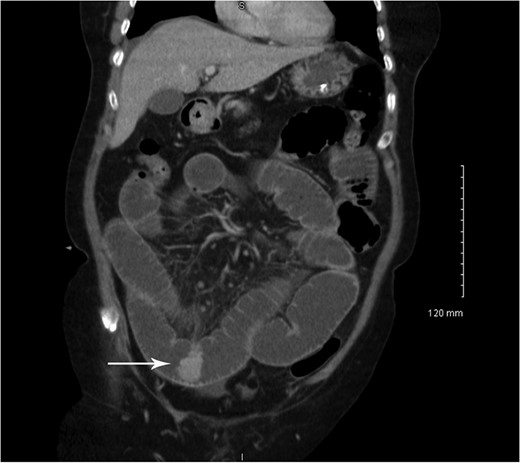

Coronal CT showing small bowel to small bowel intussusception (arrow).